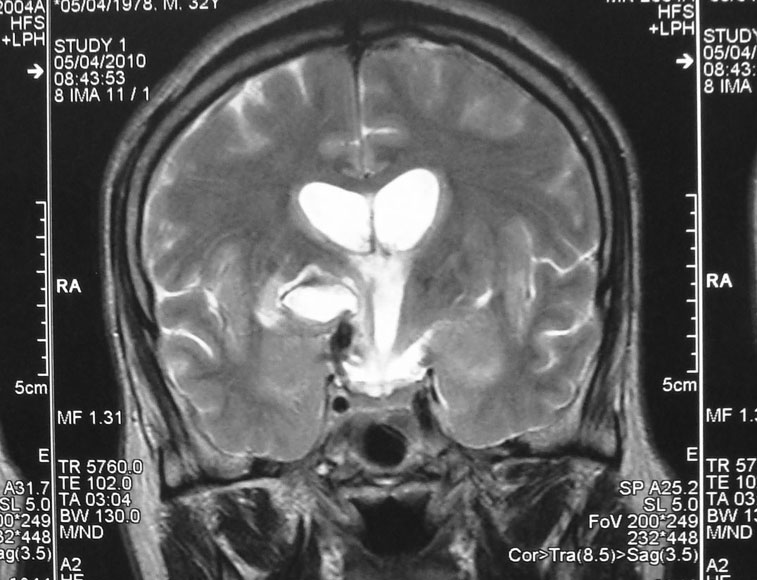

Pilocytic astrocytoma of Posterior Third Ventricle

A 9-year-old male child was evaluated for recurring headaches. Clinically, he had papilloedema. Imaging studies (Figs 1 to 3a & b) showed large posterior third ventricular tumor exhibiting peripheral rim contrast enhancement. The tumour was excised under general anaesthesia, in sitting position, by Supracerebellar Infratentorial approach. The tumour could be excised completely. He has been followed up, and MRI after three years showed only postoperative changes and no tumour residue (Figs 4a & b).